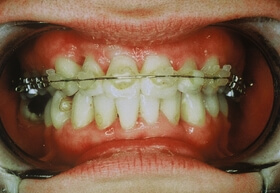

A fogágybetegség kezelése után a beteg fogszabályozó készüléket kap az esztétikai eltérés korrekciójára

A kezelés végén a fogszabályozó készülék eltávolítása előtt

A végeredmény, a frontfogak a belső oldalon összesínezve